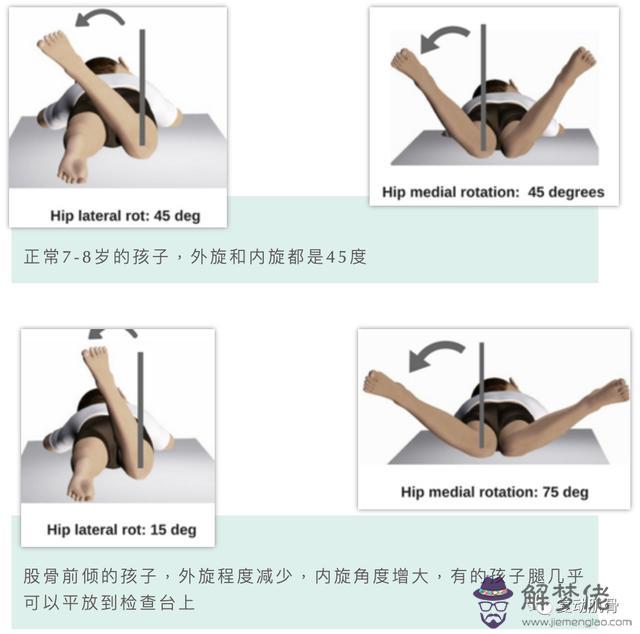

股骨前傾是造成3歲以上兒童步態異常最常見的原因,它是由股骨內旋引起的。到了12歲時,骨骼才會逐漸保持穩定的狀態。從12-16歲開始,隨著成年年齡的增長,這種變化會減小

標志和癥狀

▶1.股骨與脛骨之間的旋轉角度逐漸變小,通常到了12歲會有所緩解,同時家長需要經常觀察孩子的膝蓋和腳的位置變化。

▶2.進行相關運動訓練以刺激增加髖關節外旋的能力,增加髖外旋的柔韌性。

▶3.如果病情比較嚴重(內旋角度大于80度,外旋小于10度)并且伴有跌倒或嚴重的體態問題,則可以考慮在10歲以后進行手術。